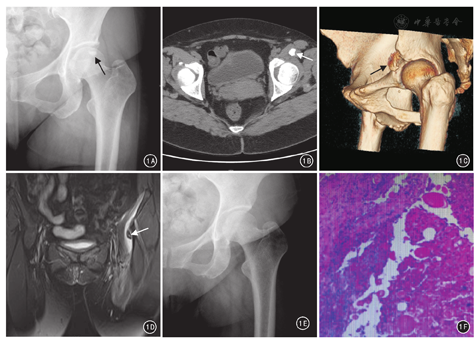

患者女,44岁,"左髋关节疼痛伴活动受限20 d"入院。患者发病前自感左髋部不适,活动后加重,20 d前无明显诱因下出现左侧髋关节针刺样剧痛,于当地医院"抗感染治疗"效果欠佳,遂转入徐州医科大学附属医院关节外科进一步治疗。患者平素体健,无严重基础疾病,否认外伤史。体格检查:左髋部皮肤温度、颜色正常,左下肢肌力Ⅳ级,左腹股沟点深压痛阳性,左髋关节各方向主动、被动活动明显受限,以外展为著。左腹股沟疼痛VAS 5分。实验室检查:外周血WBC 6.8×109/L,中性粒细胞比例0.59,淋巴细胞比例0.36,红细胞沉降率63 mm/1 h,C反应蛋白20.40 mg/L。影像学检查:双髋关节正位X线片示左髋臼缘骨皮质欠光整,局部斑片状骨密度影(图1A);髋关节CT三维重建示左侧髋臼前上缘骨质形态不整,股直肌起点部示结节状骨样密度影,边缘示小片状高密度影(图1B、图1C);髋关节MRI平扫示左侧髋臼前上方骨质示斑片状短T2信号影,临近软组织示片状长T2信号影(图1D)。初步诊断为:左髋部钙化性肌腱炎。于2017年3月3日在全身麻醉下行左髋关节钙化灶清除术。于左髂前上棘下2 cm处作一3.5 cm斜切口,逐层剥离软组织,在左髂前下棘前下方见一1 cm×2 cm灰白色钙化灶,用髓核钳取出并送病理检查。术后第3天复查髋关节正位X线片,未见左髋关节钙化灶(图1E)。病理检查结果:软骨组织内见纤维组织增生,炎细胞浸润,内见多量钙化小体(图1F)。术后第2天,患者左髋关节疼痛明显减轻,可自主行走,VAS 2分;术后第3天,局部疼痛症状完全消失;术后8个月随访,左髋部主动活动正常,活动后髋关节无疼痛感。

影像学检查对髋部钙化性肌腱炎的辅助诊断及与其他骨科常见疾病的鉴别诊断具有重要意义。X线片可较直观地观察到病变处高密度影,不难与骨恶性肿瘤鉴别;CT三维重建可更具体地辨识出病变部位、大小、形状及其与周围组织的关系;MRI在该病急性期多呈现出短T2、长T1低信号及周围软组织长T1、长T2水肿影,CT和MRI影像学检查相结合对于手术方案的制定具有指导作用[5]。此外,超声检查、发射单光子计算机断层扫描仪及PET-CT对于诊断该病具有独特价值[6,7],临床上常用于该病的辅助诊断和治疗。